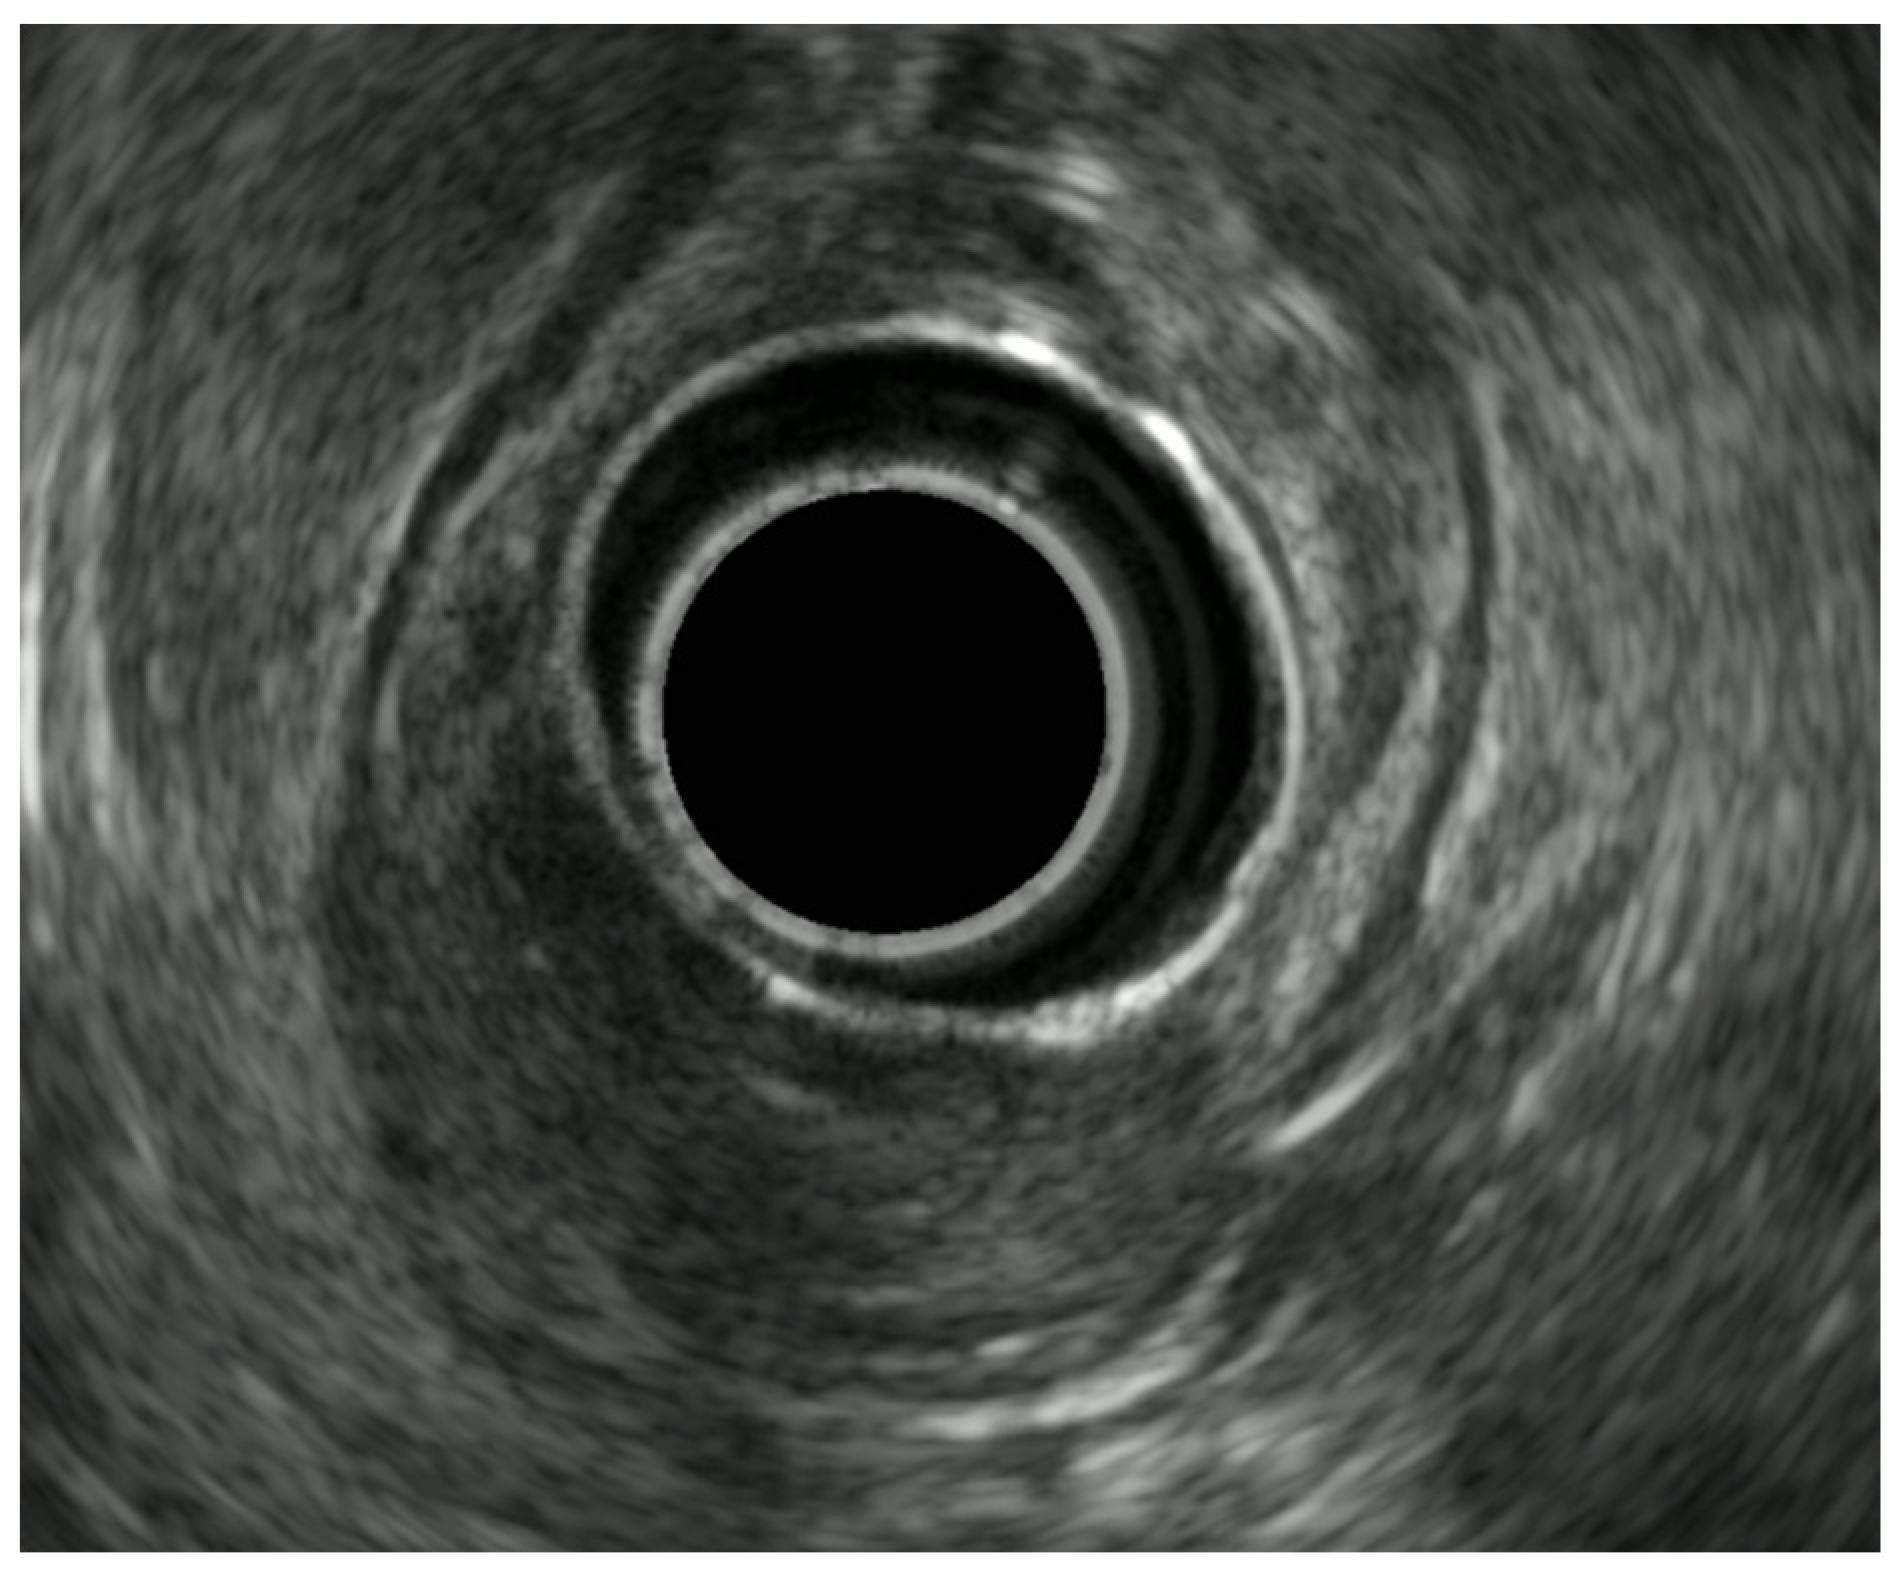

8.3. Rectal Subepithelial Lesions

- Hwang, J.H.; Saunders, M.D.; Rulyak, S.J.; Shaw, S.; Nietsch, H.; Kimmey, M.B. A prospective study comparing endoscopy and EUS in the evaluation of GI subepithelial masses. Gastrointest. Endosc. 2005, 62, 202–208. [Google Scholar] [CrossRef]

- Chen, H.-T.; Xu, G.-Q.; Teng, X.-D.; Chen, Y.-P.; Chen, L.-H.; Li, Y.-M. Diagnostic accuracy of endoscopic ultrasonography for rectal neuroendocrine neoplasms. World J. Gastroenterol. 2014, 20, 10470–10477. [Google Scholar] [CrossRef] [PubMed]

- Pagano, N.; Ricci, C.; Brighi, N.; Ingaldi, C.; Pugliese, F.; Santini, D.; Campana, D.; Mosconi, C.; Ambrosini, V.; Casadei, R. Incidental diagnosis of very small rectal neuroendocrine neoplasms: When should endoscopic submucosal dissection be performed? A single ENETS centre experience. Endocrine 2019, 65, 207–212. [Google Scholar] [CrossRef] [PubMed]